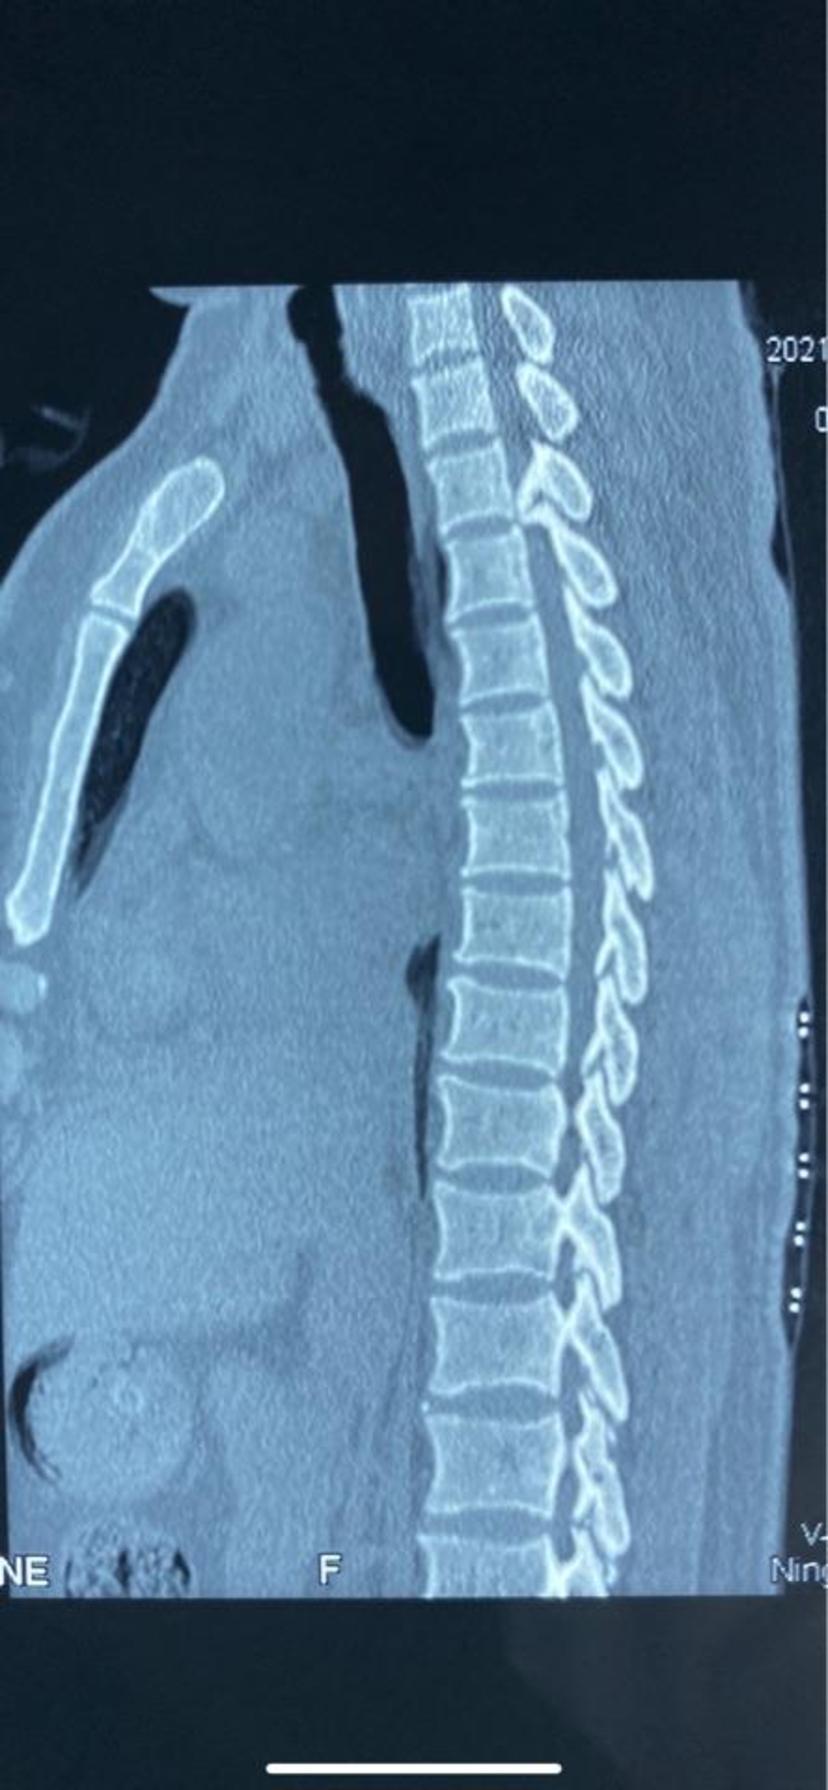

黎燕清,女,56岁,胸椎后凸畸形,t8,9椎体骨折,as并al,op,清远职工医保

术前核磁:胸12-腰1椎间盘突出,胸椎管狭窄.内镜术中清晰显露硬膜囊.